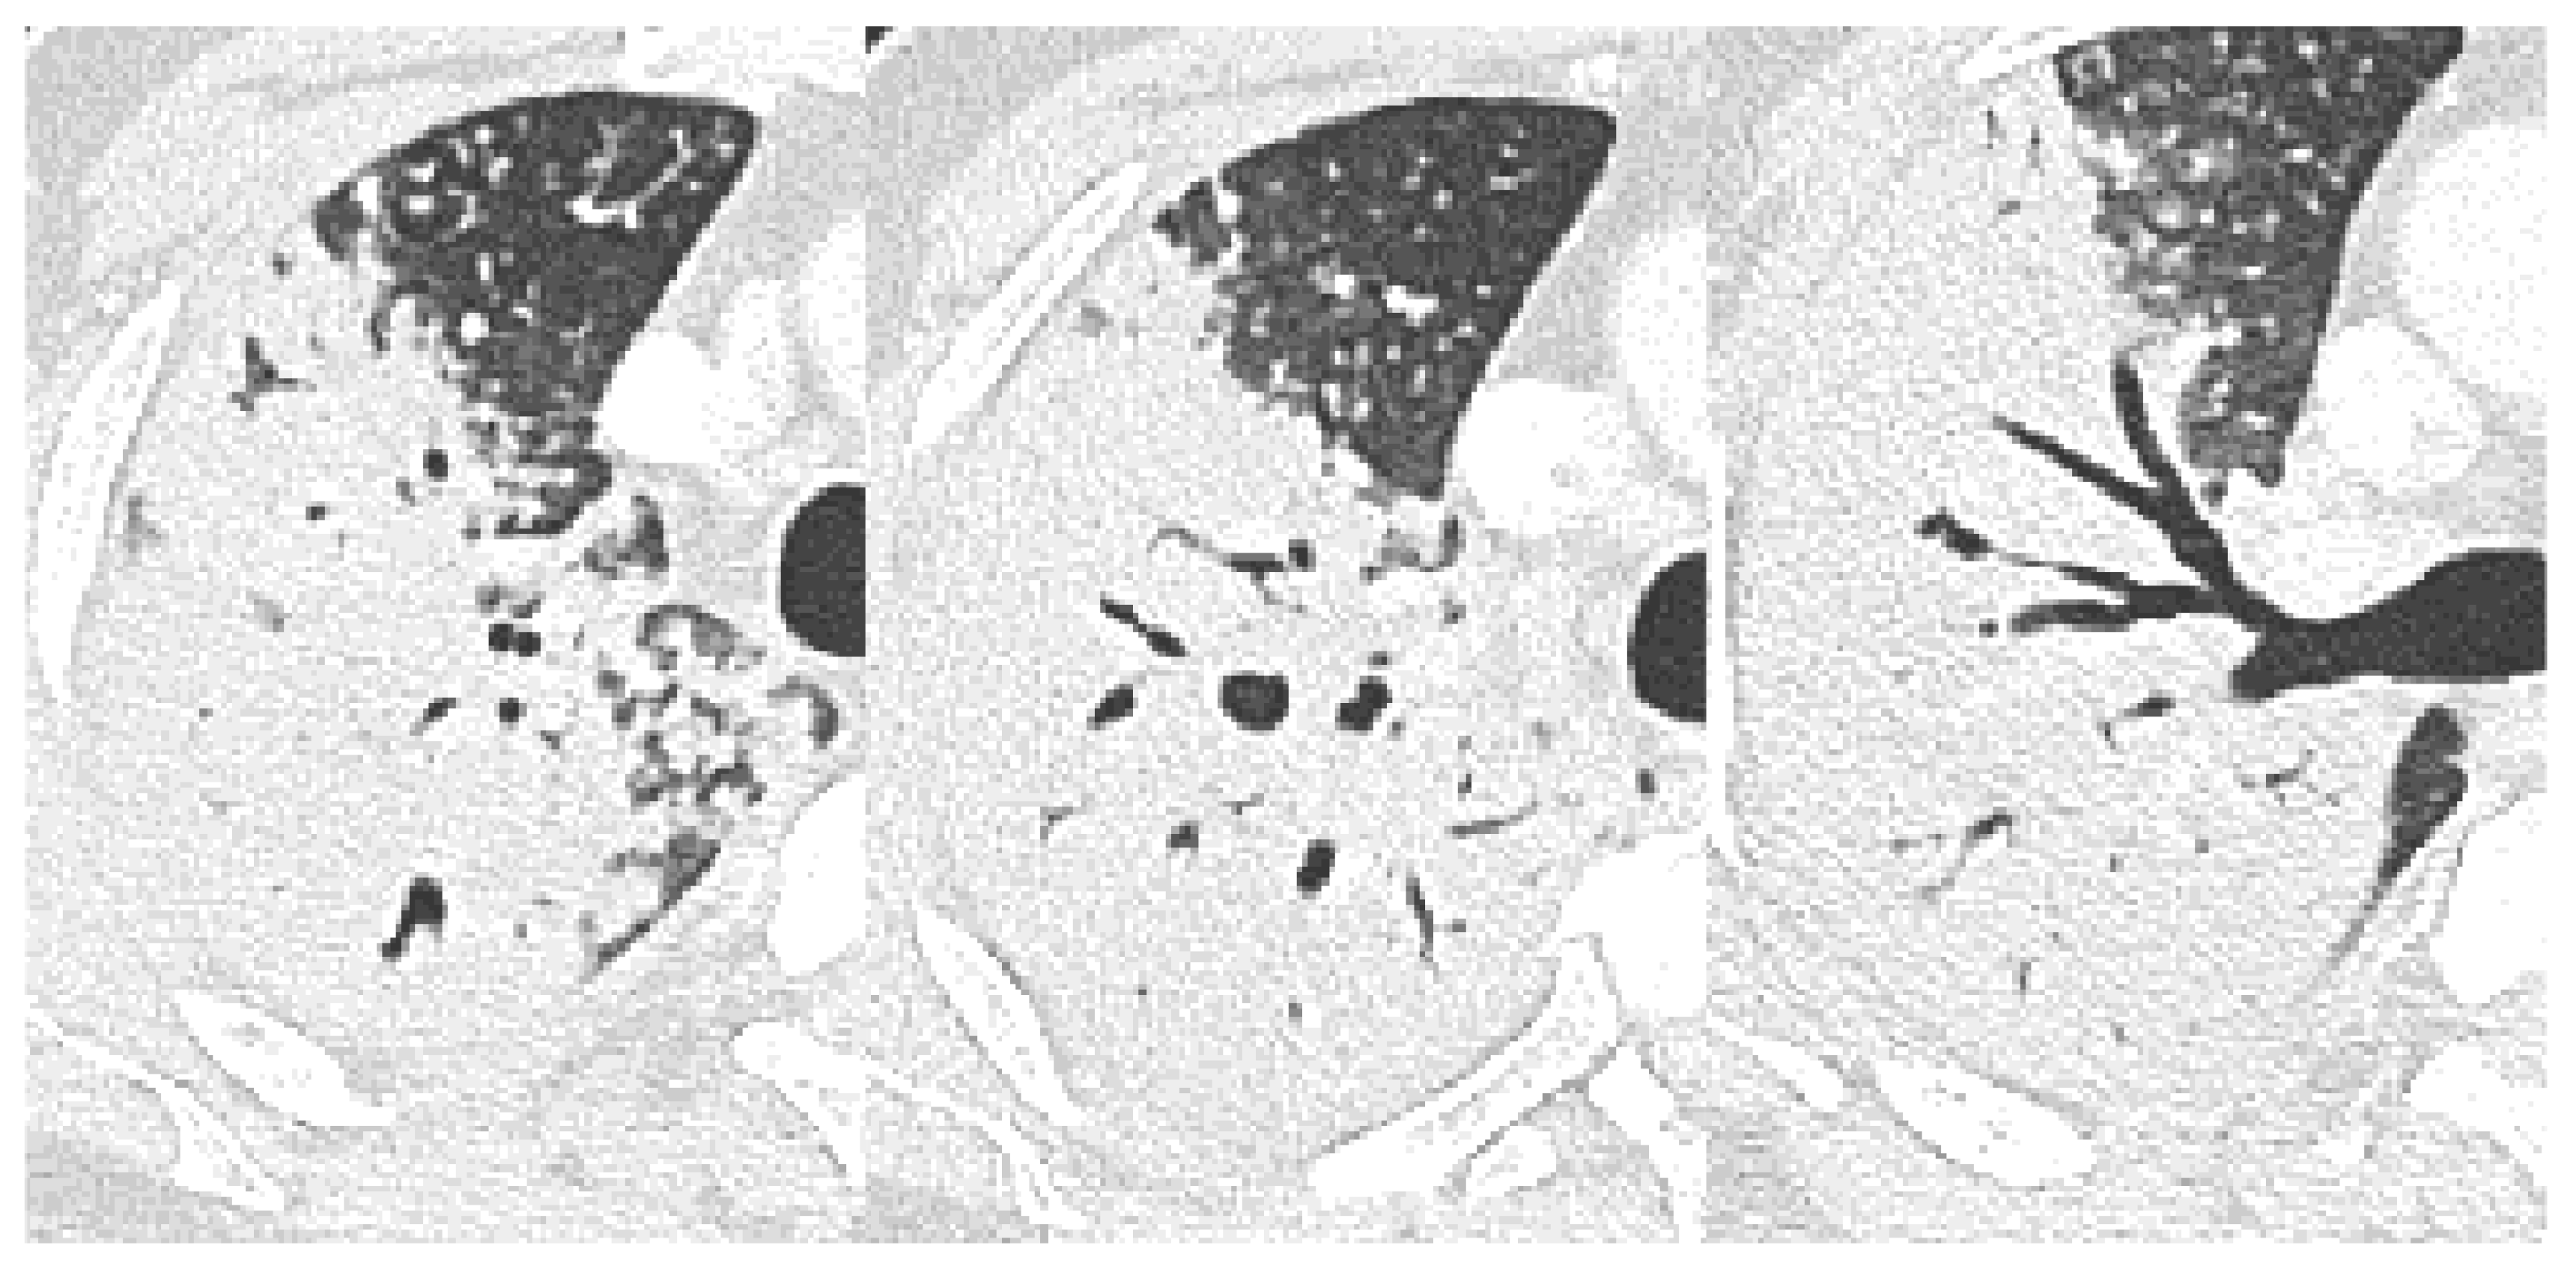

| Bronchial erosion | 157 (47) | 110 (44) | 9 (30) | 38 (73) | <0.001 | 0.157 | <0.001 | <0.001 |

| Cavitation | 157 (47) | 109 (43) | 7 (23) | 41 (79) | <0.001 | 0.038 | <0.001 | <0.001 |